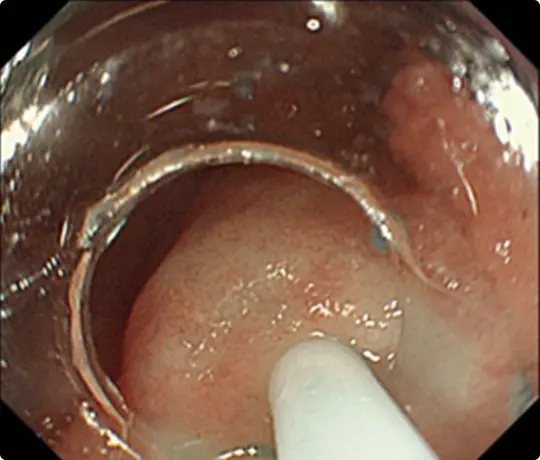

全周性のESD後です。穿孔(壁に穴があくこと)などの問題なく、病変を切除しました。切除後は潰瘍が出来ますが、1~2ヵ月で治ります。

食道は元々細いため、大きな病変を切除した後は、潰瘍の治癒に伴い食道がより細くなり、ご飯が通らなくなる場合があります。近年、ステロイドの注射で細くなるのを予防出来ることが分かって来ました。

当科でも広範な食道ESD後はステロイドを注射し、食道が細くなるのを予防しています。